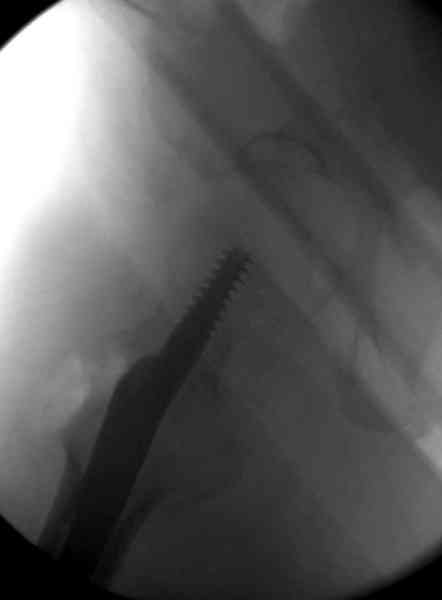

Здесь сканнированные снимки импланта и операционные снимки больной.

На этом снимке процесс компрессии нижним болтом.